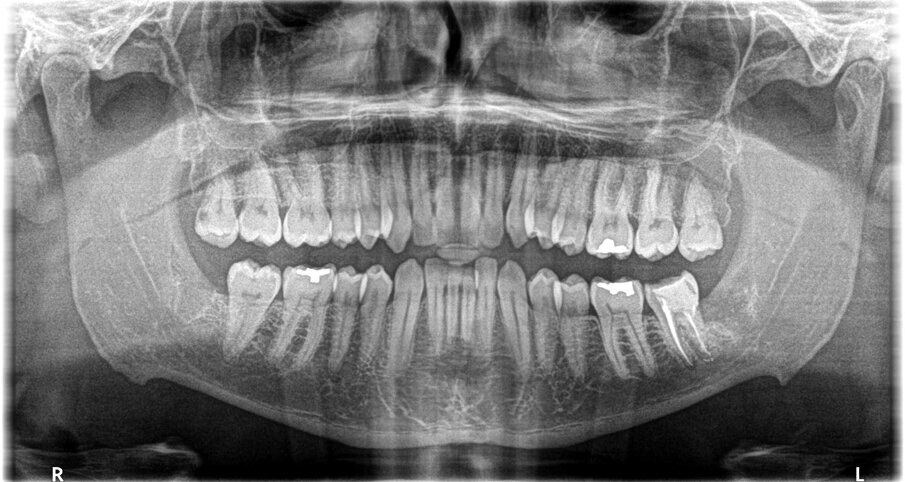

A questo proposito si presenta il caso della paziente F.C., 48 anni, che presentava un 3.8 in seminclusione. A livello anamnestico la paziente riferiva a carico del suddetto elemento, reiterati episodi flogistici e algici. A livello radiografico veniva inoltre riscontrata la presenza di una importante lesione cariosa sulla superficie distale del contiguo 3.7 (Fig. 1). Si è pertanto deciso di procedere alla estrazione chirurgica del 3.8 secondo tecnica convenzionale con incisione e scollamento del lembo muco-periosteo, ostectomia vestibolo-mesiale, avulsione dell’elemento dentario curetage dell’alveolo residuo e sutura a mezzo di punti staccati. L’intera seduta si è svolta senza complicazioni e ha avuto la durata complessiva di 25 minuti. (Fig. 2)

Fig. 1 - Particolare dell’ortopantomografia che evidenzia tra l’altro il danno indotto dal 3.8 semincluso sulla superficie distale del contiguo 3.7.